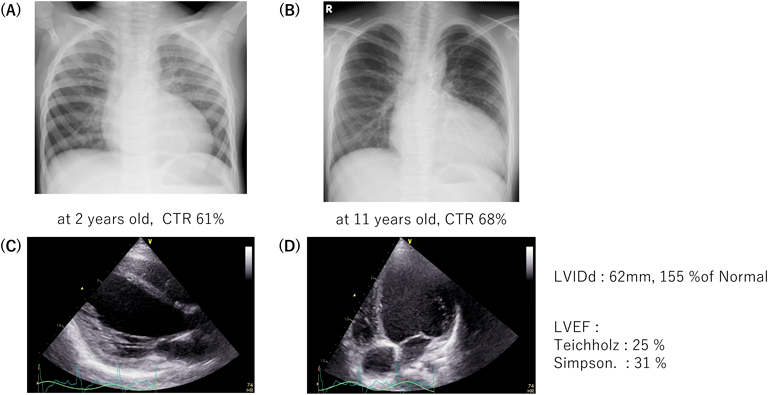

Fig. 1 症例1の胸部レントゲンと心エコー図

(A) 2歳時,(B) 11歳時,(C), (D) 心エコー図

11歳時の心電図は洞調律のLBBBで,QRS時間は170 msであった.BNP 238 pg/mL,NTproBNP 2,296 pg/mLまで上昇した.エコー所見はLVIDd 62 mm,155% of Normal,LVEFはTeichholzで25%,Simpsonで31%と低下していた(Fig. 1).

LBBBの左室非同期による心不全症例でCRTの適応と判断した.11歳で体重は身長142 cm,38 kgの体格に対して,経静脈的にCRTPデバイスの植込みを行った.CRTにより,心電図のQRS時間は170 msから150 msに短縮した(Fig. 2).

胸部レントゲンCTRは術前の68%から3か月後には56%,4年後には52%に改善した.

心エコーのLVIDdは62 mm,155% of Nから4年後には46 mm,93% of N,LVEFはTeichholzで25%から62%,Simpsonで31%から54%まで改善した.臨床的にも活発になり,運動時の息切れなども消失した.生活管理指導区分は「D」で管理中である.